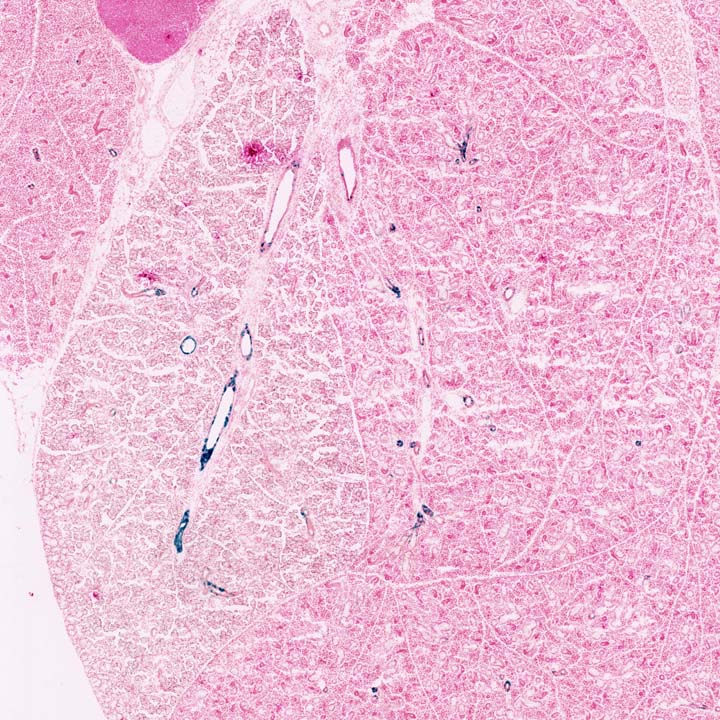

This transgene expresses Cre recombinase in the liver, under the control of an albumin promoter (species not specified).

Tg(Alb1-cre)1Dlr activity also observed in: